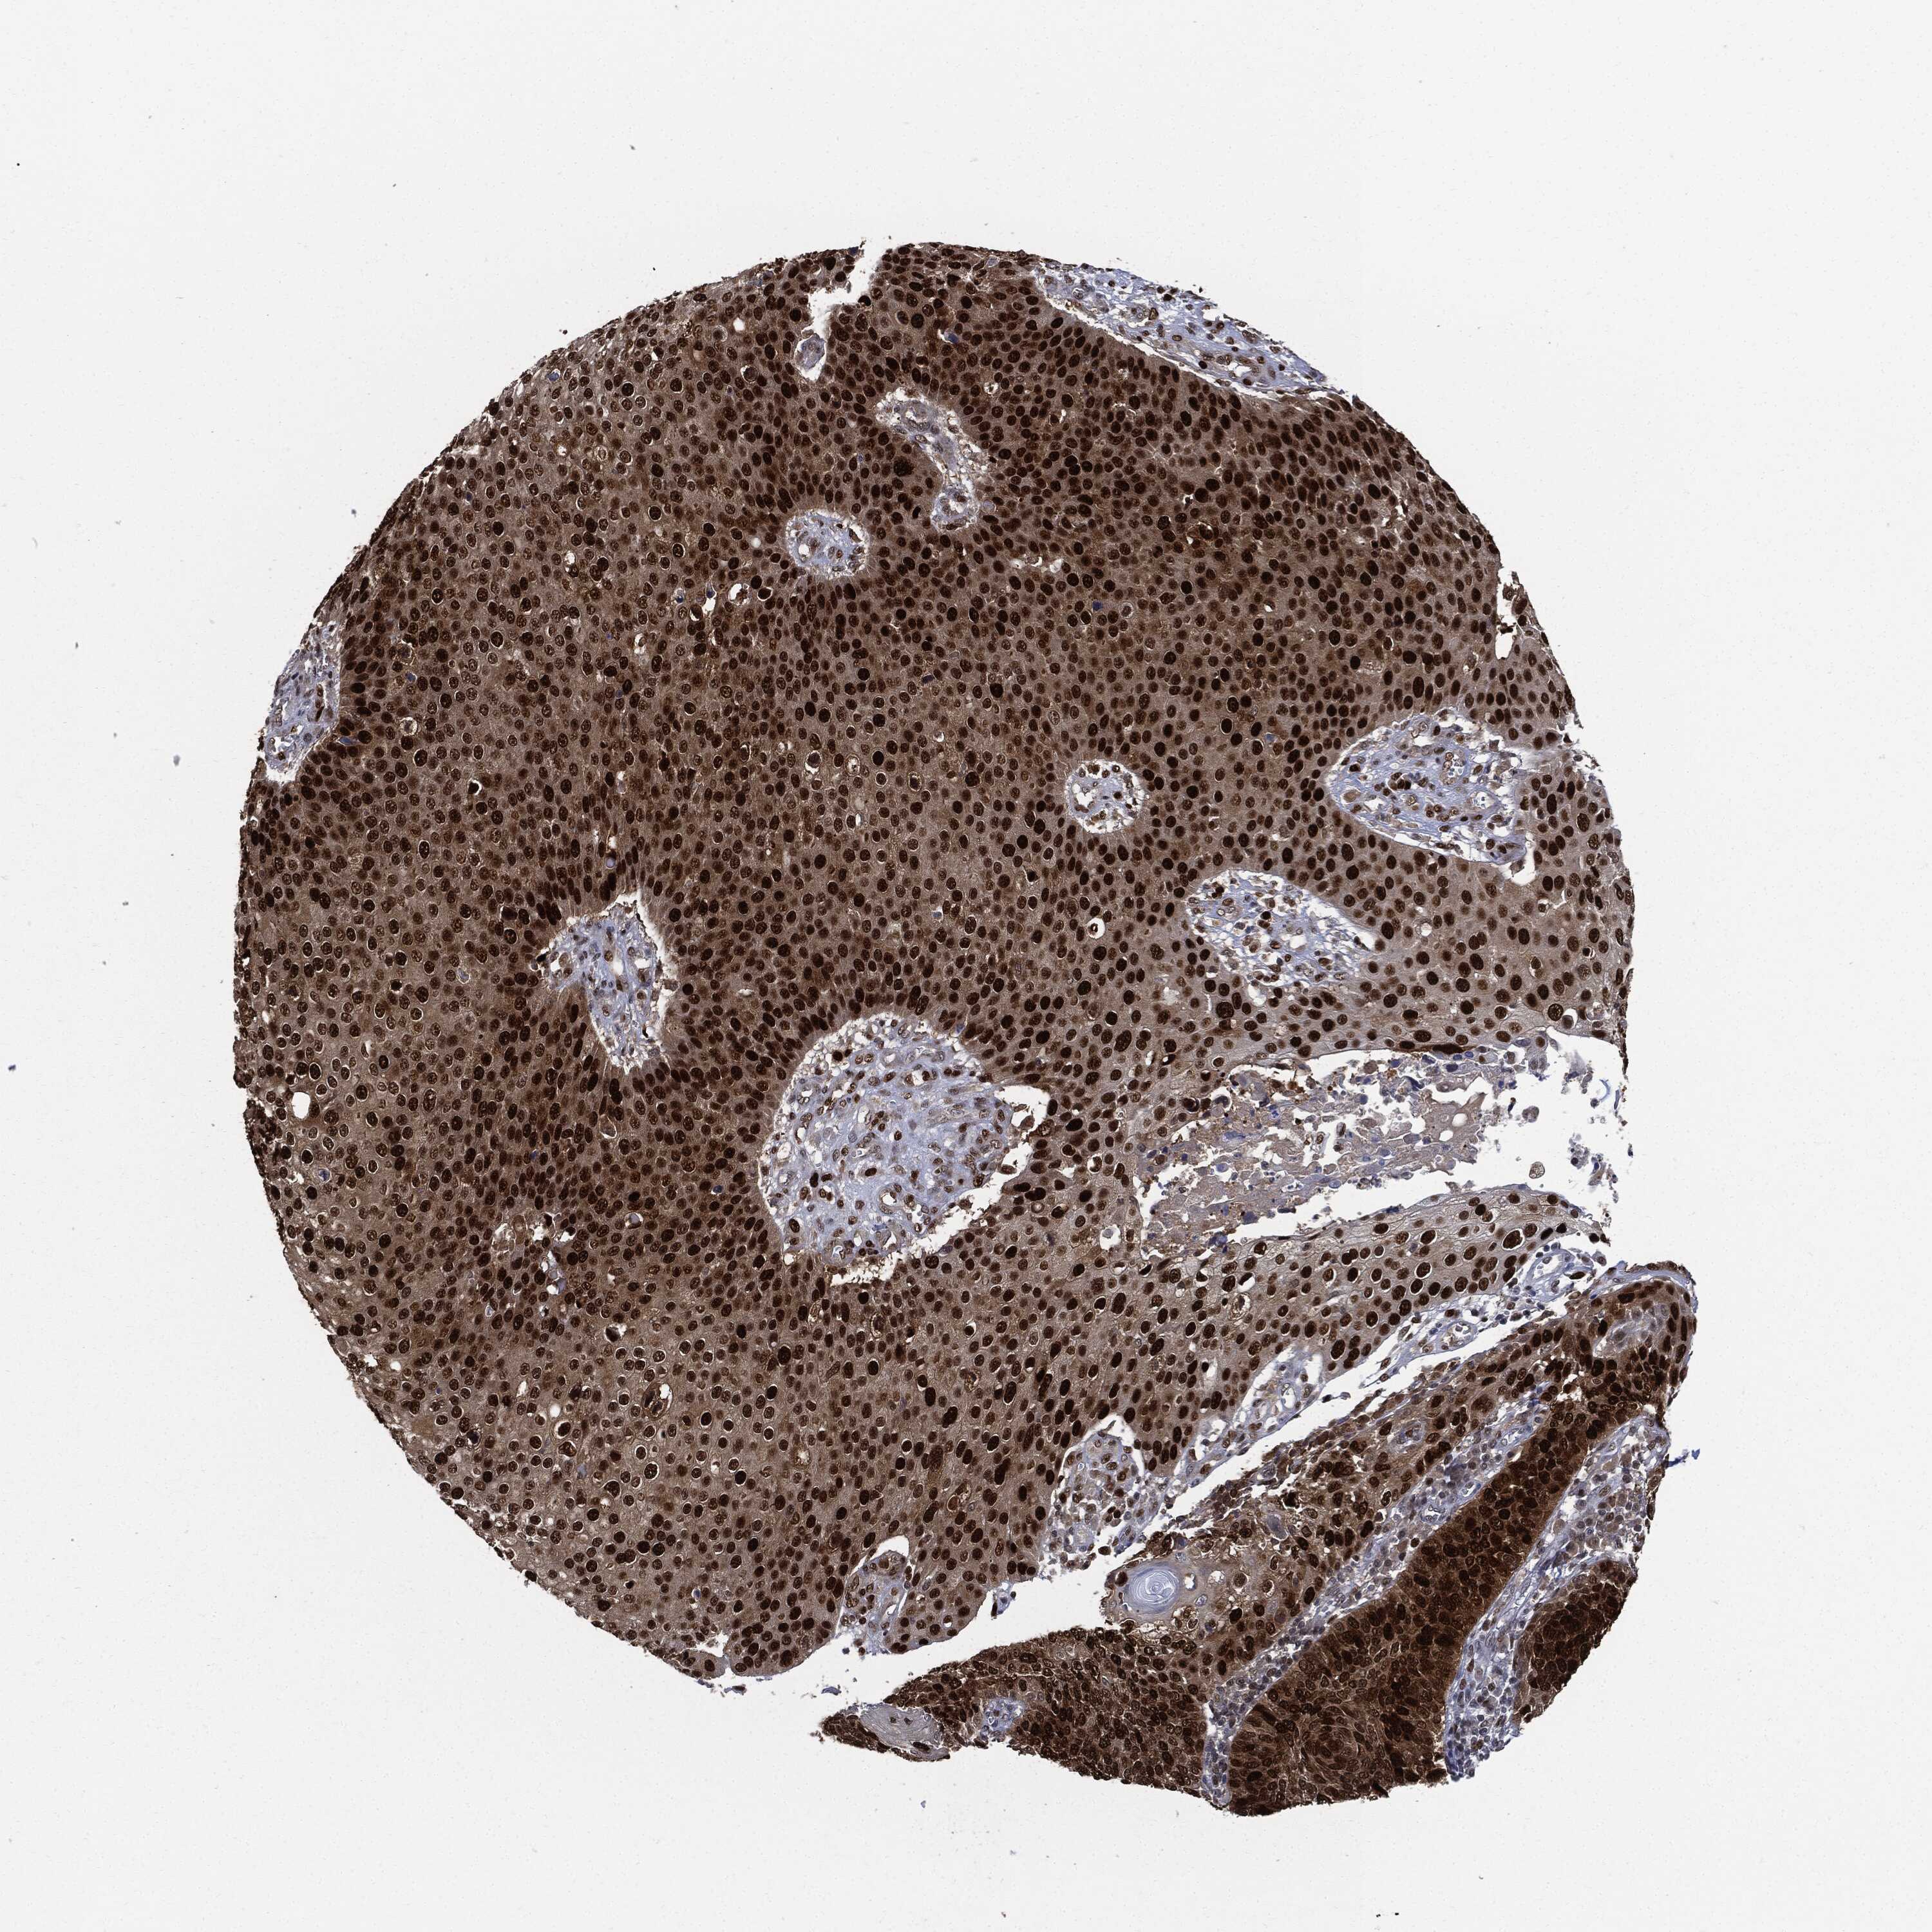

SKIN CANCER - Protein expressioni

A mouse-over function shows sample information and annotation data. Click on an image to view it in a full screen mode. Samples can be filtered based on level of antibody staining by selecting one or several of the following categories: high, medium, low and not detected. The assay and annotation is described here.

Each image is clickable and will lead to virtual microscopy that enables deeper exploration of all samples and also displays staining intensity scores, fraction scores and subcellular localization as well as patient and tissue information for each sample.

Staining

High

Medium

Low

Not detected

Intensity

Strong

Moderate

Weak

Negative

Quantity

>75%

75%-25%

<25%

None

Location

Nuclear

Cytoplasmic/membranous

Cytoplasmic/membranous,nuclear

Basal cell carcinoma

Squamous cell carcinoma, NOS

Squamous cell carcinoma, metastatic, NOS